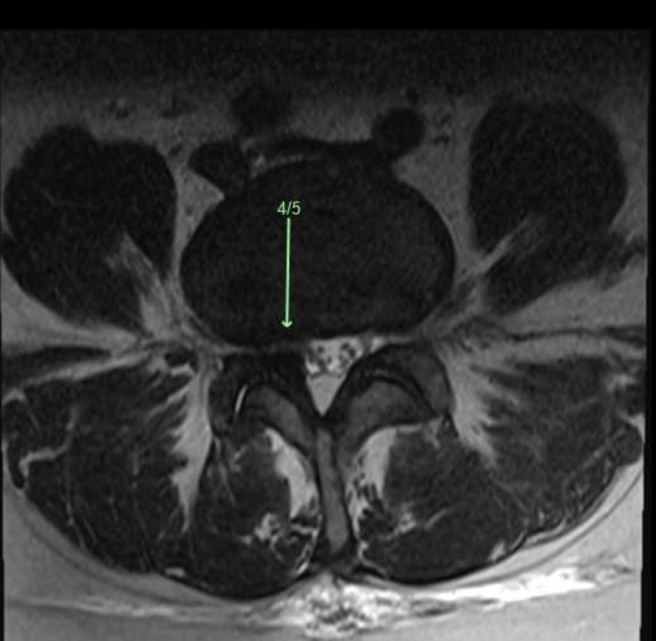

This is what mild central canal stenosis looked like on my MRI nine months ago.

You can see when comparing the two MRI images, where the issue is (green arrow courtesy of Radiologists).